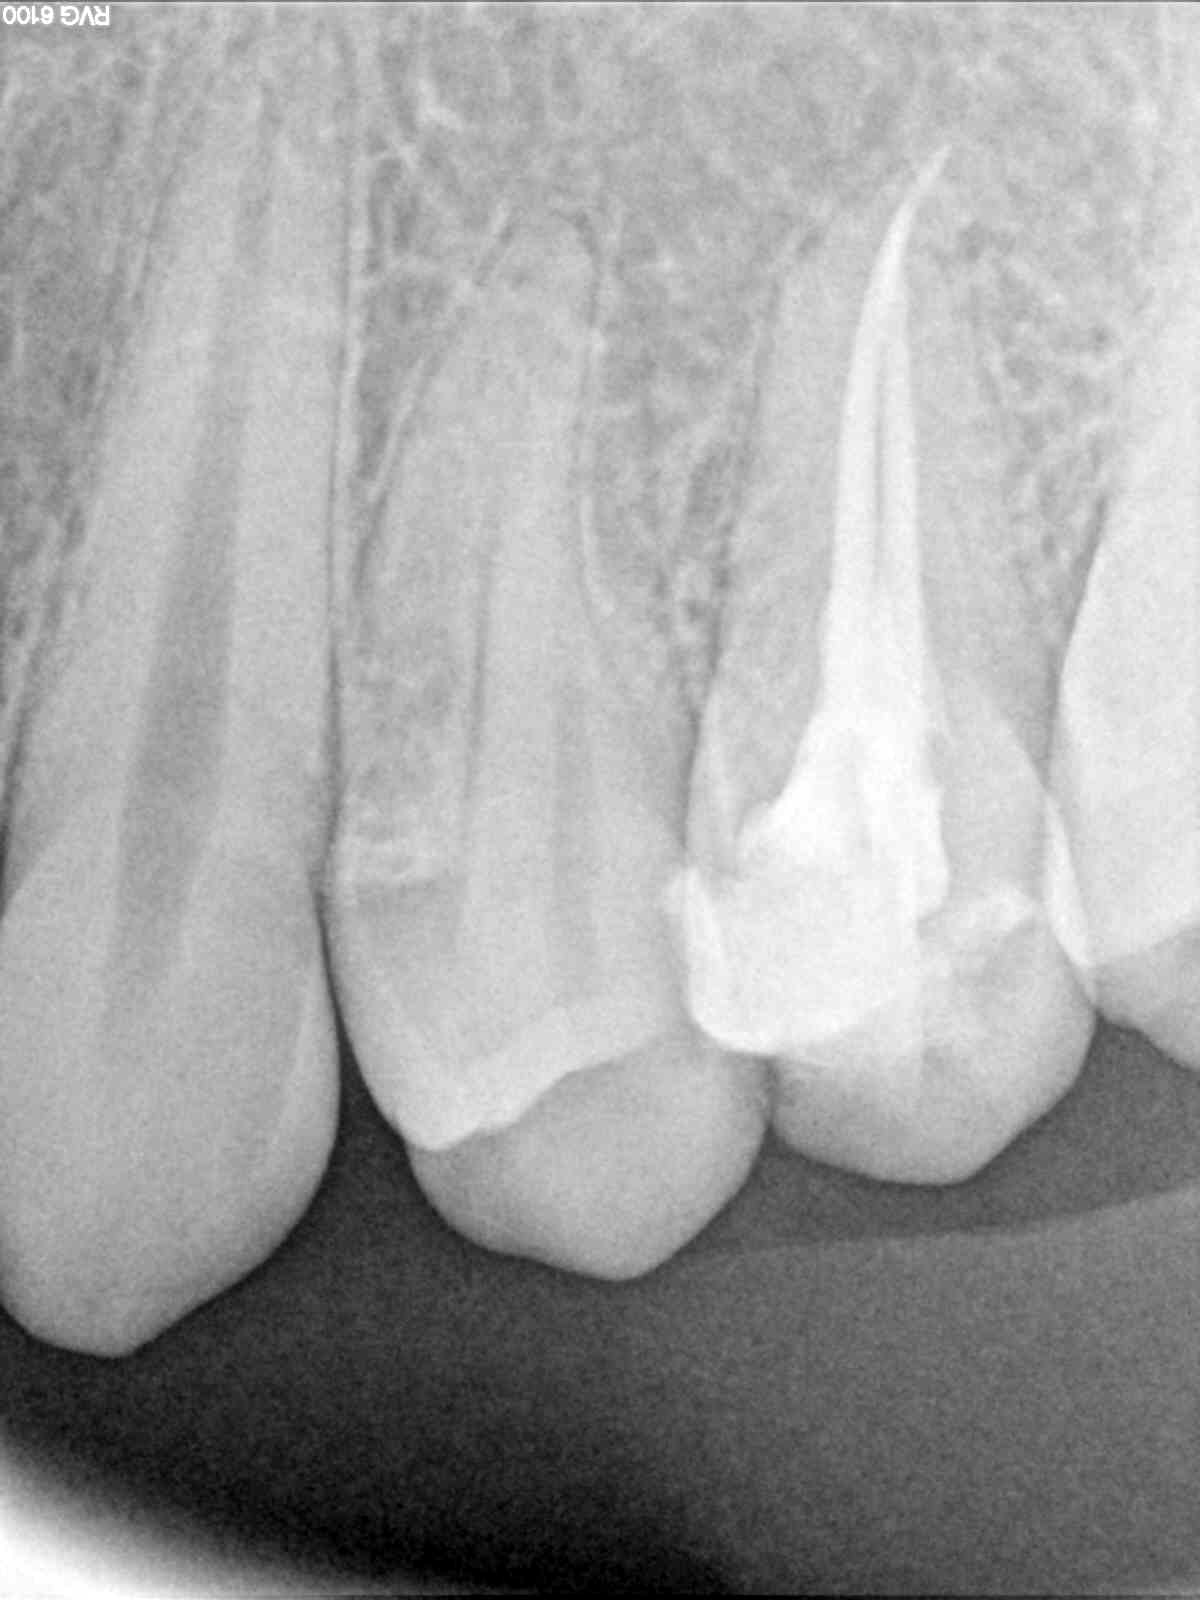

Heppp , on se calme ; aucun mépris la dedans , juste un peu d'humour pour désamorcer la discussion qui ne mène nulle part puisque nous ne serons jamais d'accord ! tiens une devinette toute fraîche (à l'instant ) et qui pourra alimenter votre parano de dentistes sous payés : où est l'endo faite en France ( par bibi ) pour 100 balles et celle faite au canada pour 600 ou 700 balles ? ( les 2 à 6 mois d'écart ) . Prix / qualité , on disait ? ( les prix sont arrondis pour les pointilleux qui scrutent la moindre erreur ...) . Et dire que les vendeurs de matos sont les mêmes pour ces 2 pays amis (!) , cherchez l'erreur ou tout simplement n'y aurait-il pas un peu d'abus par là ....